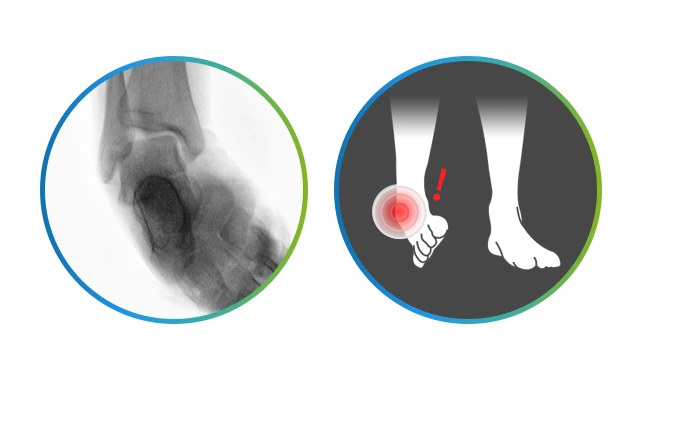

발목연골손상

발목연골손상.PNG

가장 흔한 원인이 외상인 발목연골손상의 평균 발생 연령은 20~30대입니다. 증상으로는 발목 관절의 부종, 통증, 잠김 현상이지요. 발목에서 소리가 나거나 관절에서 걸리는 느낌이 있는 경우, 발목 손상 이후 지속적인 통증과 불편함이 있는 경우, 발목 관절의 움직이는 정도가 감소된 경우, 손가락으로 눌렀을 때 발목에 통증이 있는 경우라면 발목연골손상을 의심해볼 수 있습니다.

갑자기 발목의 심한 통증이 있다가 자연적으로 좋아지는 증상이 반복되는 것이 특징인데요 이런 증상들을 대수롭지 않게 여겨 방치하게 되면 관절염으로 진행된답니다.